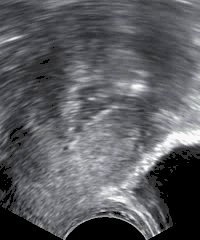

| Sonohysterography performed because of postmenopausal bleeding. In serial images, polyps would be more immobile than freely moving debris within the uterine cavity which are seen in the image. | |